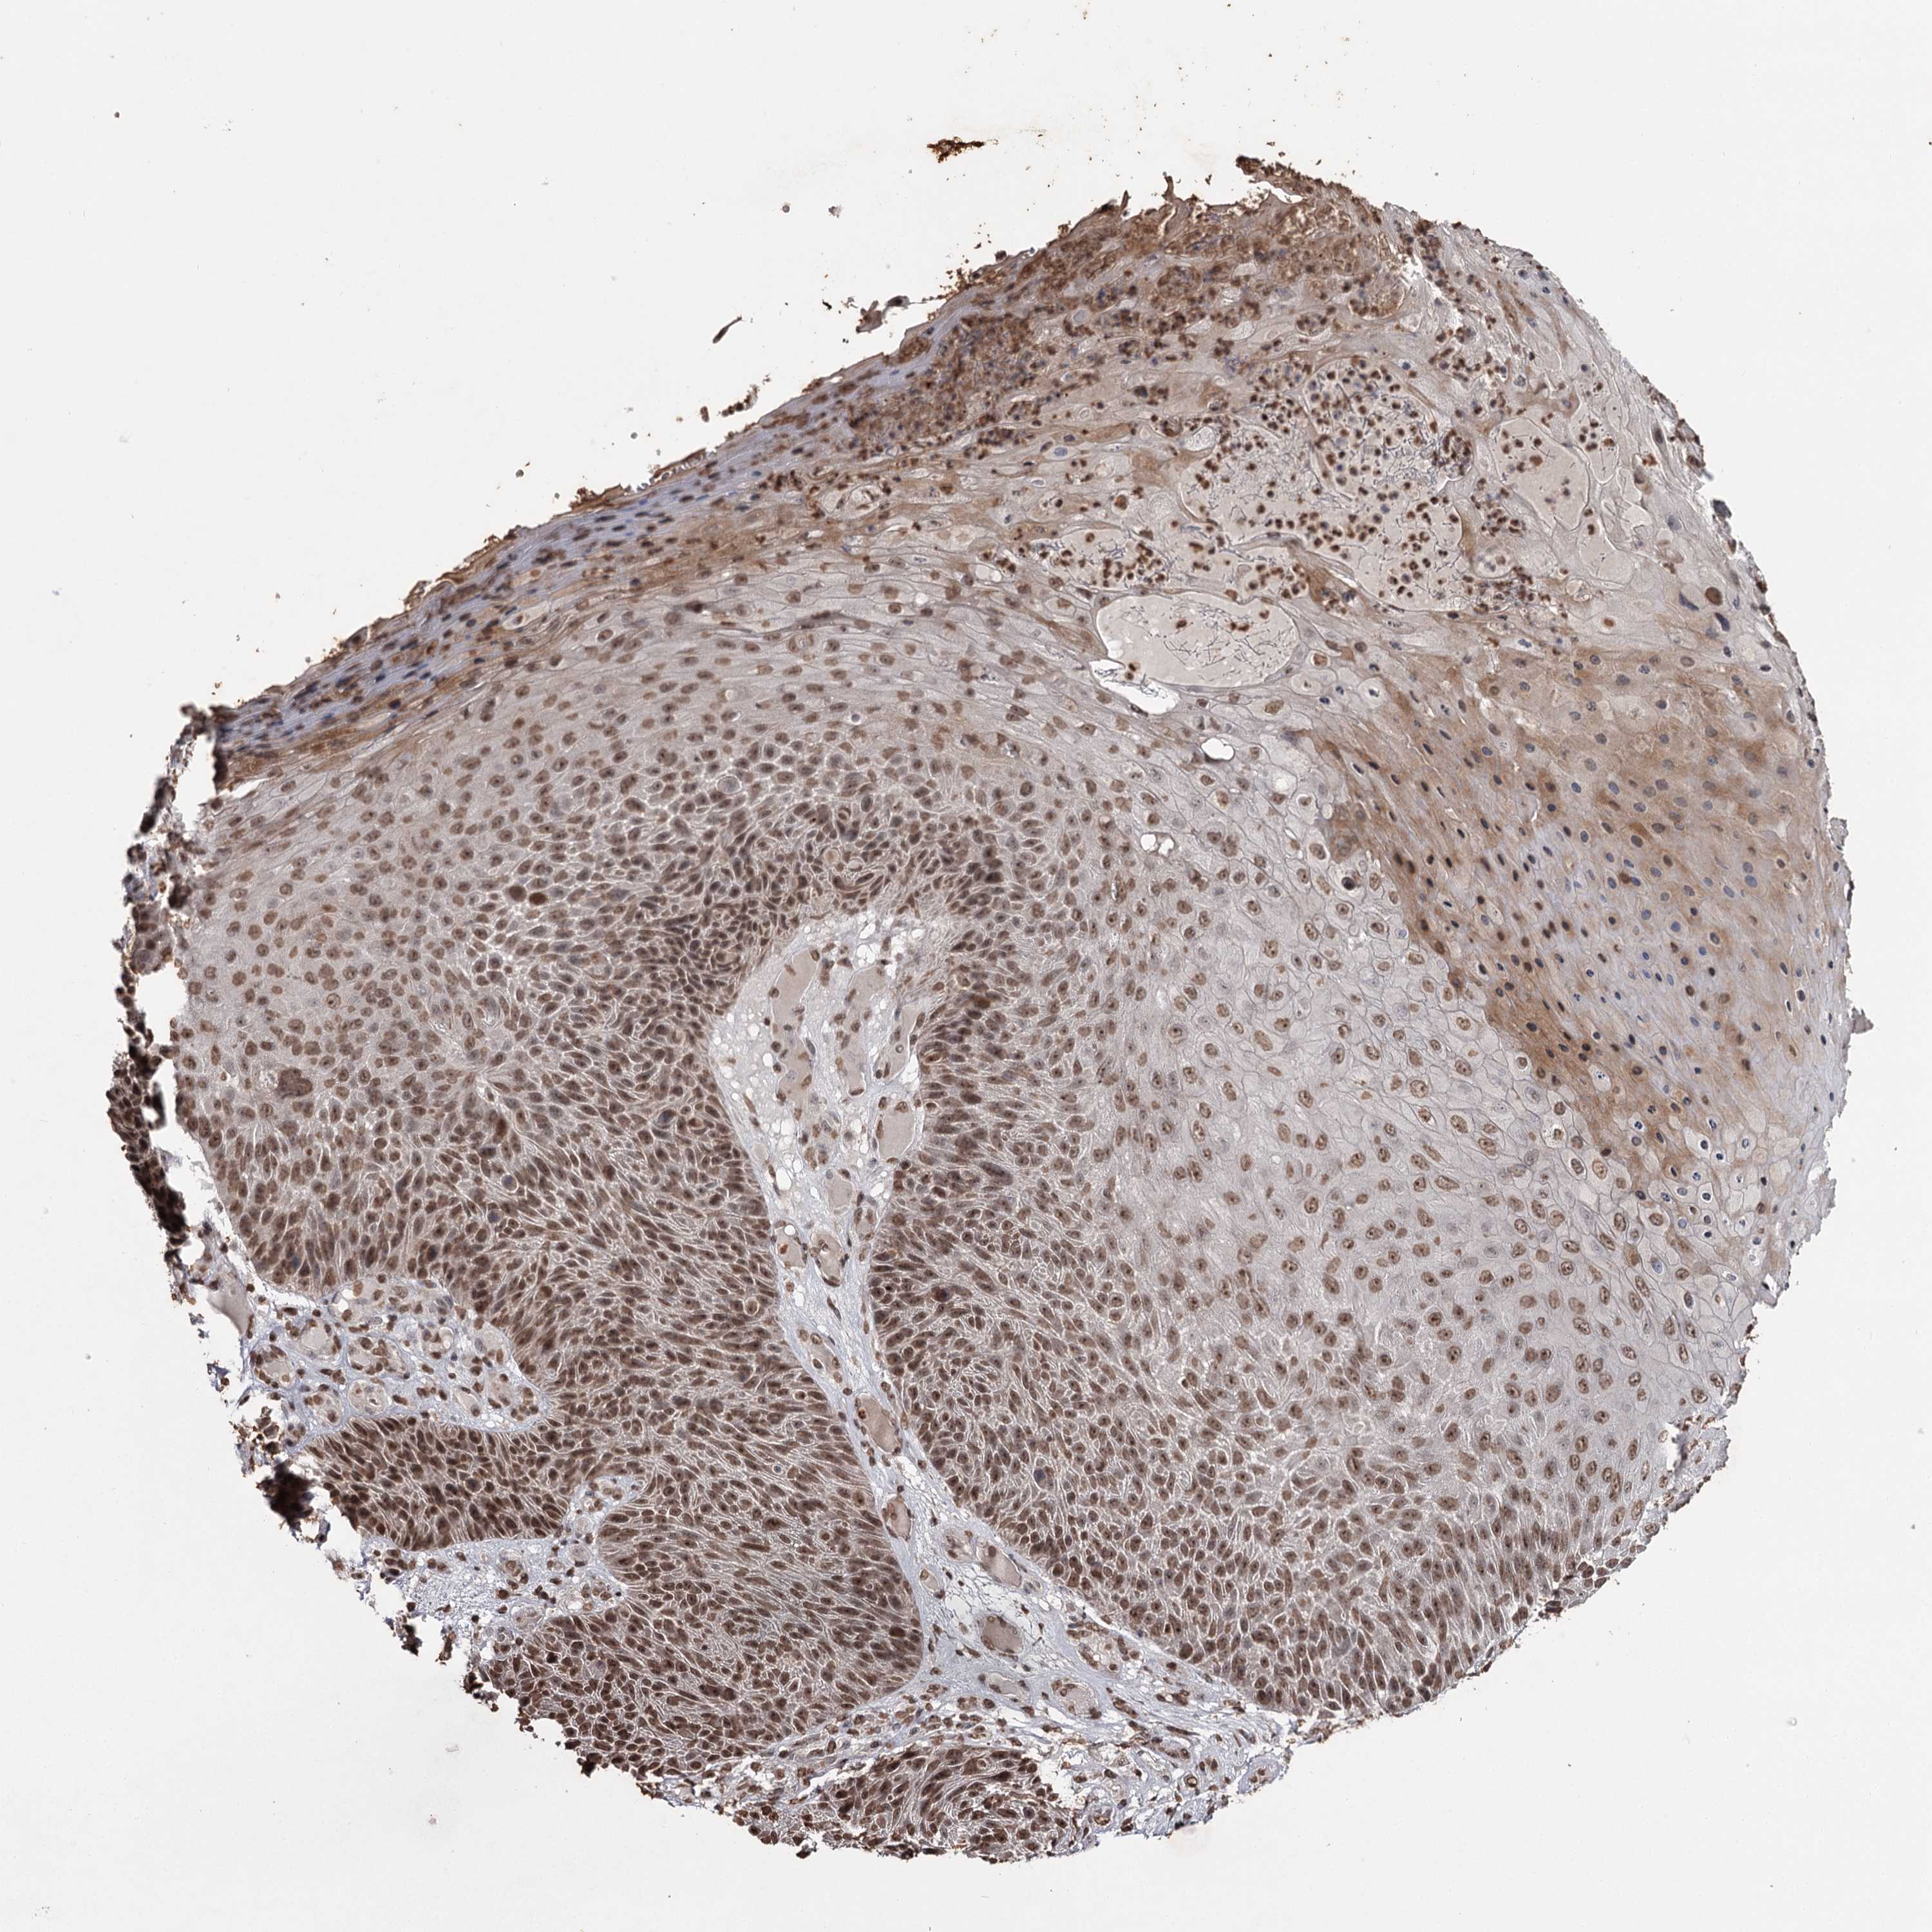

SKIN CANCER - Protein expressioni

A mouse-over function shows sample information and annotation data. Click on an image to view it in a full screen mode. Samples can be filtered based on level of antibody staining by selecting one or several of the following categories: high, medium, low and not detected. The assay and annotation is described here.

Antibody staining in the annotated cell types in the current human tissue is reported as not detected, low, medium, or high, based on conventional immunohistochemistry profiling in selected tissues. This score is based on the combination of the staining intensity and fraction of stained cells.

Each image is clickable and will lead to virtual microscopy that enables deeper exploration of all samples and also displays staining intensity scores, fraction scores and subcellular localization as well as patient and tissue information for each sample.

Antibody HPA038732

Squamous cell carcinoma, NOS